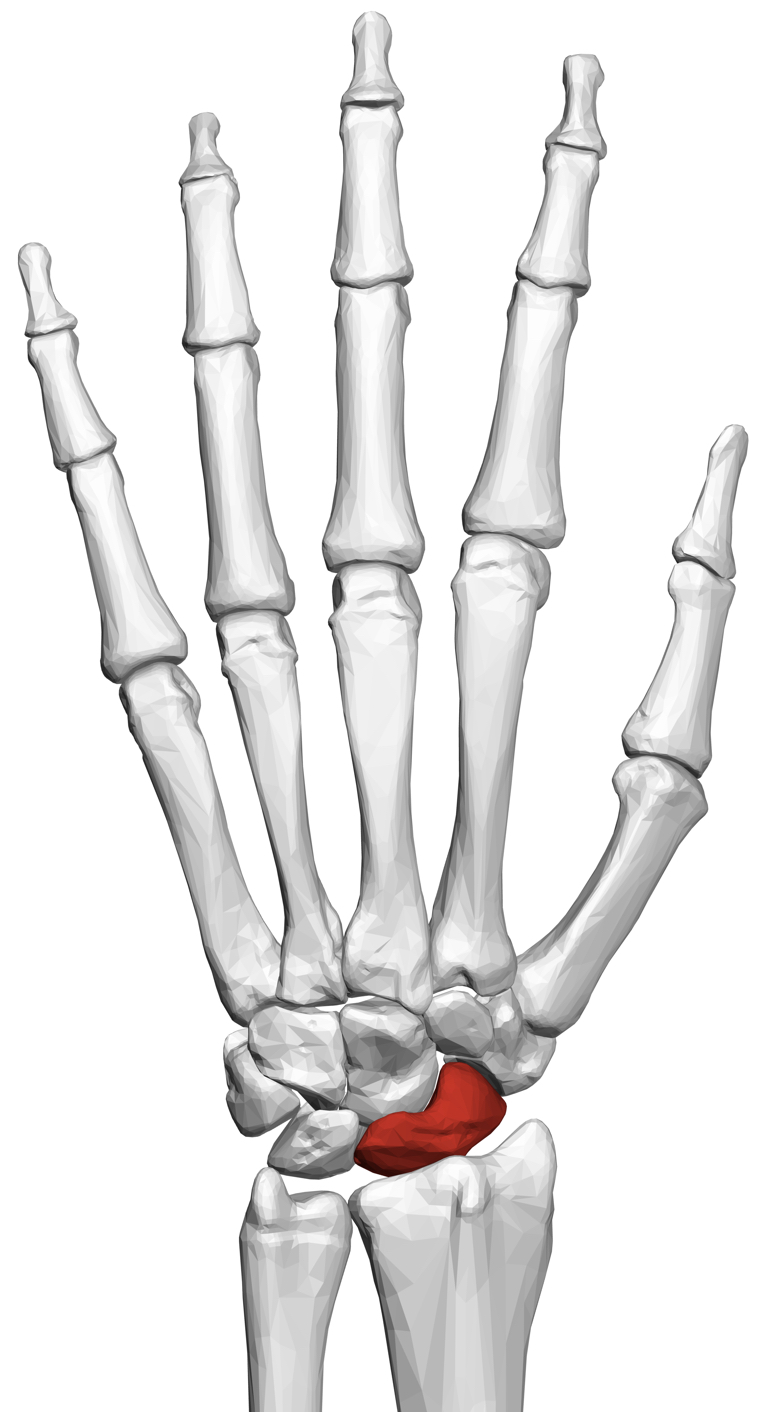

تحدث الدكتور أحمد إبراهيم صالح، مدرس جراحة العظام بكلية طب جامعة المنصورة، عن كسر العظمة الزورقية، موضحًا أن عظمة الزورقية واحدة من 8 عظمات في المعصم ومسئولة بنسبة 80 % عن تحويل الحمل من الذراع إلى اليد، وبالتالي هي المسئولة عن نقل قوة الذراع من أعلى إلى أسفل.

وذكر مدرس جراحة العظام، أن تشخيص كسر العظمة الزورقية يكون عن طريق عمل أشعة، ويتم إعادتها مرة أخرى بعد عشر أيام حتى حال كانت النتيجة جيدة بالإضافة إلى ارتداء جبيرة اليد خلال هذه الفترة، وفي حالة وجود كسر يتم إجراء أشعة مقطعية للاطمئنان على شكل الكسر.

ويتساءل الكثير من الناس عن علاج كسر العظمة الزورقية؟ وحول هذا التساؤل يُجيب الدكتور أحمد إبراهيم صالح، موضحًا أن العلاج يكون سهل ومباشر ويتخلف على حسب حالة الكسر كما يلي:

- إذا كان الكسر في المنطقة الوسطى يتم إجراء جبس كامل لمدة 4 أشهر مع المتابعة.

- أما إذا كان الكسر في منطقة الساعد يحتاج إلى تثبيت بمسمار هربرت، وذلك عن طريق إجراء فتحة صغيرة لا تتجاوز الـ 5 سنتي في باطن اليد أو ظهرها.